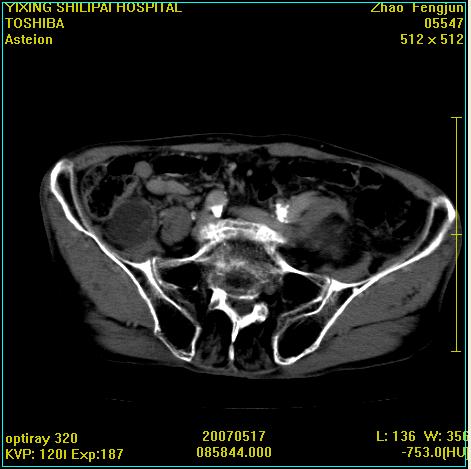

考虑:1、左侧腰大肌囊实性占位性病变(囊性神经根鞘瘤?);

2、右侧兰尾区囊性占位性病变(兰尾囊肿?囊腺癌?类癌?)

以下是引用xiaoniu在2007-5-26 10:45:00的发言:[br]腰大肌的病变应该没有问题,增强扫描还有轻度强化及细小血管影入内,应该排除脓肿,考虑占位性病变,腰大肌的占位多考虑:神经源性肿瘤。另外腹主动脉下端有真假腔的强化,考虑:主动脉夹层。[br][br][本贴已被 xiaoniu 于 2007-5-26 10:46:39 修改过]

以下是引用老爱克斯新网客在2007-5-26 18:26:00的发言:[br]1左下腹囊实性占位肿块,增强后不均匀强化,位于脊柱旁,椎体骨质无破坏软组织无肿胀,考虑神经源肿瘤神经鞘瘤可能大,2右下腹囊性占位性病变,增强后囊壁强化,考虑阑尾囊肿或囊腺瘤,